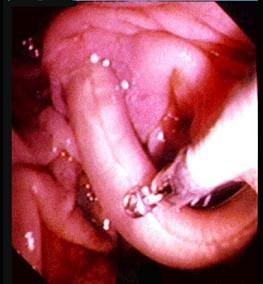

选项 A、阑尾炎的压痛、反跳痛主要在右下腹 B、胆道蛔虫病常出现腹膜刺激征 C、胃、十二指肠溃疡穿孔的压痛、反跳痛以上腹部最明显 D、胰腺炎病人血尿淀粉酶增高 E、胆总管结石的腹痛常伴发热和黄疸